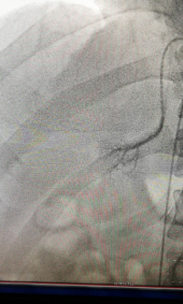

?——我院成功開展雙側(cè)腎上腺靜脈插管采血術(shù)?近日,我院心內(nèi)科、檢驗(yàn)科、內(nèi)分泌科、泌尿外科多科協(xié)作,成功開展了雙側(cè)腎上腺靜脈插管采血術(shù)。該項(xiàng)高血壓診療新技術(shù)目前只在國內(nèi)少部分醫(yī)院開展。我院首次開展此項(xiàng)技術(shù)后,明確了患者高血壓的病因,實(shí)現(xiàn)了高血壓的精準(zhǔn)治療,標(biāo)志著該院對高血壓的診治水平提高到了一個(gè)新的臺...